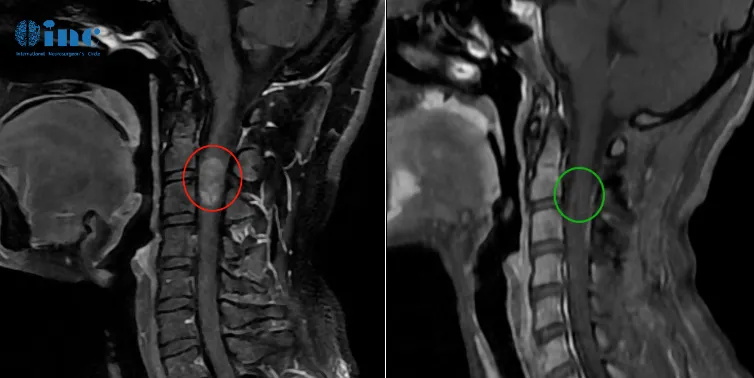

1、50岁男性——脊髓髓内室管膜瘤

病情回顾:50岁的刘先生,2年前因颈部及肩部疼痛就医检查出脊髓髓内肿瘤。由于肿瘤生长在高段颈髓内,被脊骨包围,手术暴露困难,术中脊髓稍受挤压损伤,就可能造成长期性瘫痪。很多医生都建议保守治疗。

手术结果:手术当天,在术中神经电生理监测等高医疗设备辅助下,巴教授顺利全切肿瘤,病例诊断结果为室管膜瘤。术后3天刘先生就可以下地自如行走,术前症状大多已消失,术后无长期性并发症,也无需其他辅助治疗。

2、28岁女性脊髓髓内室管膜瘤,术后3个月恢复正常生活

术前情况:28岁的潇潇6年前开始出现肩部至腰部疼痛,而两年前,潇潇肩部后侧疼痛加剧,于当地医院行磁共振检查,提示髓内占位性病变,保守治疗无效。2021年7月行增强磁共振提示C3水平占位,直径7mm。当地医院排除炎性病变。因考虑到手术风险大,未作手术治疗。2021年10月复查磁共振提示影像较前大致相仿。2022年6月磁共振提示大小约8*12*14mm。2022年10月磁共振提示8*12*19mm。

手术结果:2022年12月4日,苏州独墅湖医院,潇潇的手术顺利进行,巴教授顺利全切潇潇脊髓髓内的肿瘤,术后一天ICU查房,潇潇已经清醒,意识清楚,四肢能够正常活动。教授表示等到术后二天潇潇就可以转入普通病房,一些不舒服的症状,例如手麻等都是正常的,不属于术后并发症,后期能够恢复正常状态。